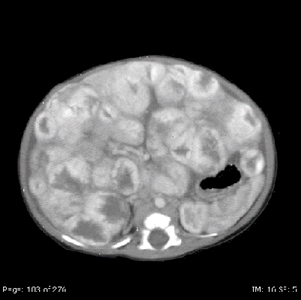

En las IRM, los tumores vasculares hepáticos son hiperintensos en las imágenes T2 e hipotensos en las imágenes T1; las imágenes después del contraste exhiben realce periférico temprano con realce difuso posterior.[

Las lesiones se suelen dividir en las siguientes 3 categorías:[

En una clasificación más adecuada se usa una evaluación interdisciplinar, que incluye la clasificación patológica con evaluación genómica, la evaluación radiológica por imagen, así como los antecedentes y exámenes clínicos; esto se fundamenta en las clasificaciones de la ISSVA y la OMS. En un estudio se analizaron 33 casos de tumores vasculares hepáticos pediátricos a partir de sus características anatomoclínicas desde 1970 hasta 2021.[